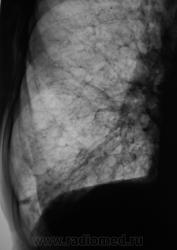

Рентгенограмма.

Диффузный пневмосклероз/пневмофиброз.

Диффузный процесс - однозначно; как то мелькнула мысль о фиброзирующем альвеолите....хотя и не факт.

Насколько я в курсе, диф.диагностика различных видов IIP и по КТ затруднительна, а уж по рутинным рентгенограммам.....

Диффузное интерстициальный процесс в обоих легких. Но меня чтото смущает кольцевидная тень в верхнем отделе слева (под ключицей). Может полостюха какая... Было бы хорошо выполнить кт, ну и конечно анамнез и клиника. IIP может быть - но надо для постановки этого диагноза исключитт все неидиопатическое - может у человека какое системное заболевание соед. Ткани или еще чего. В нашмх условиях ему бы написвли наверное диф.пневмосклероз, выставили бы хобл или ифа и лечили бы вероятнее всего гормонами сильно не заморачиваясь...

По рентгенограммам пневмофиброз, а причину фиброзирующего процессапо снимкам ... Саркоидиз, альвеолит и далее по списку...

"Сотовый" рисунок во всех отделах легочных полей.Спаечный процесс.Верхние доли тоже в свое время пострадали от туберкулеза. Похоже, жизнь была бурная-выкурено немало, может, вредное производство или системное заболевание.Уважаемые коллеги, пожалуйста, аказывайте возраст, а также анамнез, хотя бы основное.Спасибо.

картина характерна для саркоидоза. На фоне выраженного пневмофиброза очаги, легочный риснок сотовый.